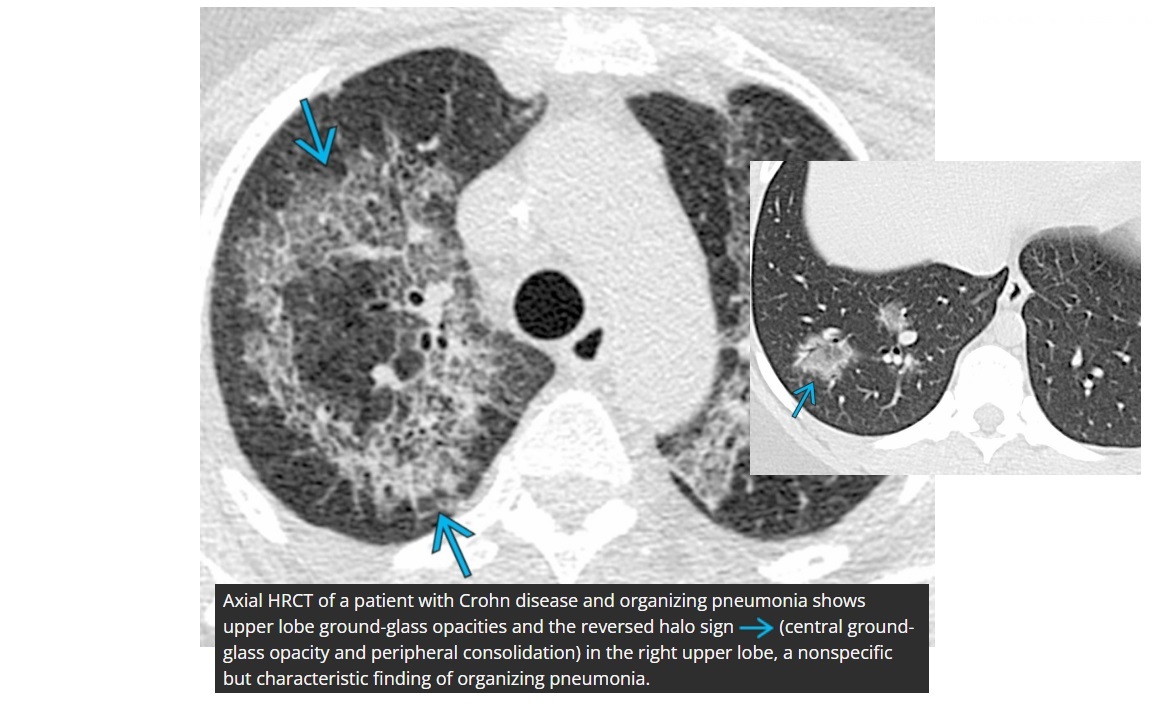

COP

Reverse halo sign

Associated with

-CF

-Methotrexate

- post-transplant

- connective tissue

Can have halo sign but more specific reverse halo sign

unlike COP, peripheral capsule in the reversed halo sign tends to be thicker